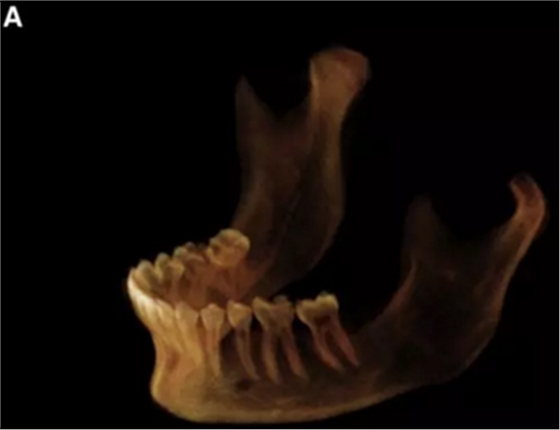

在輸出的3D模型上,使用體內(nèi)軟件(Anatomage,San Jose,Calif)將下頜骨以最小的間隔從顱骨上分離(圖5)用于保留下頜骨的咬合細(xì)節(jié),游離的下頜骨被保存(圖6,A)。同時(shí),將沒有下頜骨的顱骨導(dǎo)出并保存(圖6,B)。

圖6. A,從整個(gè)3D模型上修剪的下頜骨; B,修剪的顱骨。